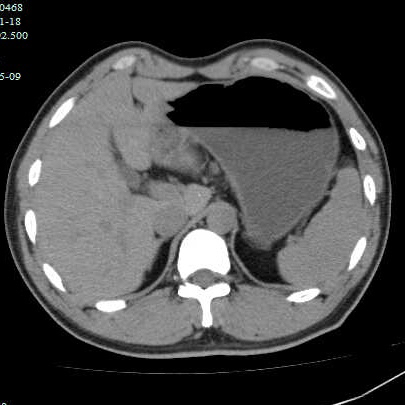

最近有几个吃山楂后形成胃结石的病历,第一个,老年女性,突发腹痛2天,持续性钝痛,阵发性加重,伴恶心,呕吐胃内容物,性状无异常,呕吐后无缓解,入院后抑酸治疗效果不理想,CT如下图。

考虑胃内结石,予以碳酸氢钠和可乐口服,第二天症状缓解,因为有别的问题,没有胃镜证实。

因为非影像专业,自己总结肠道植物性结石的特点,混杂密度,多数边缘规则,与正常胃、肠壁结构分界清晰,临床考虑多数急性起病,关键是要问近期是否有大量食用柿子、山楂、黑枣等富含鞣酸食物。